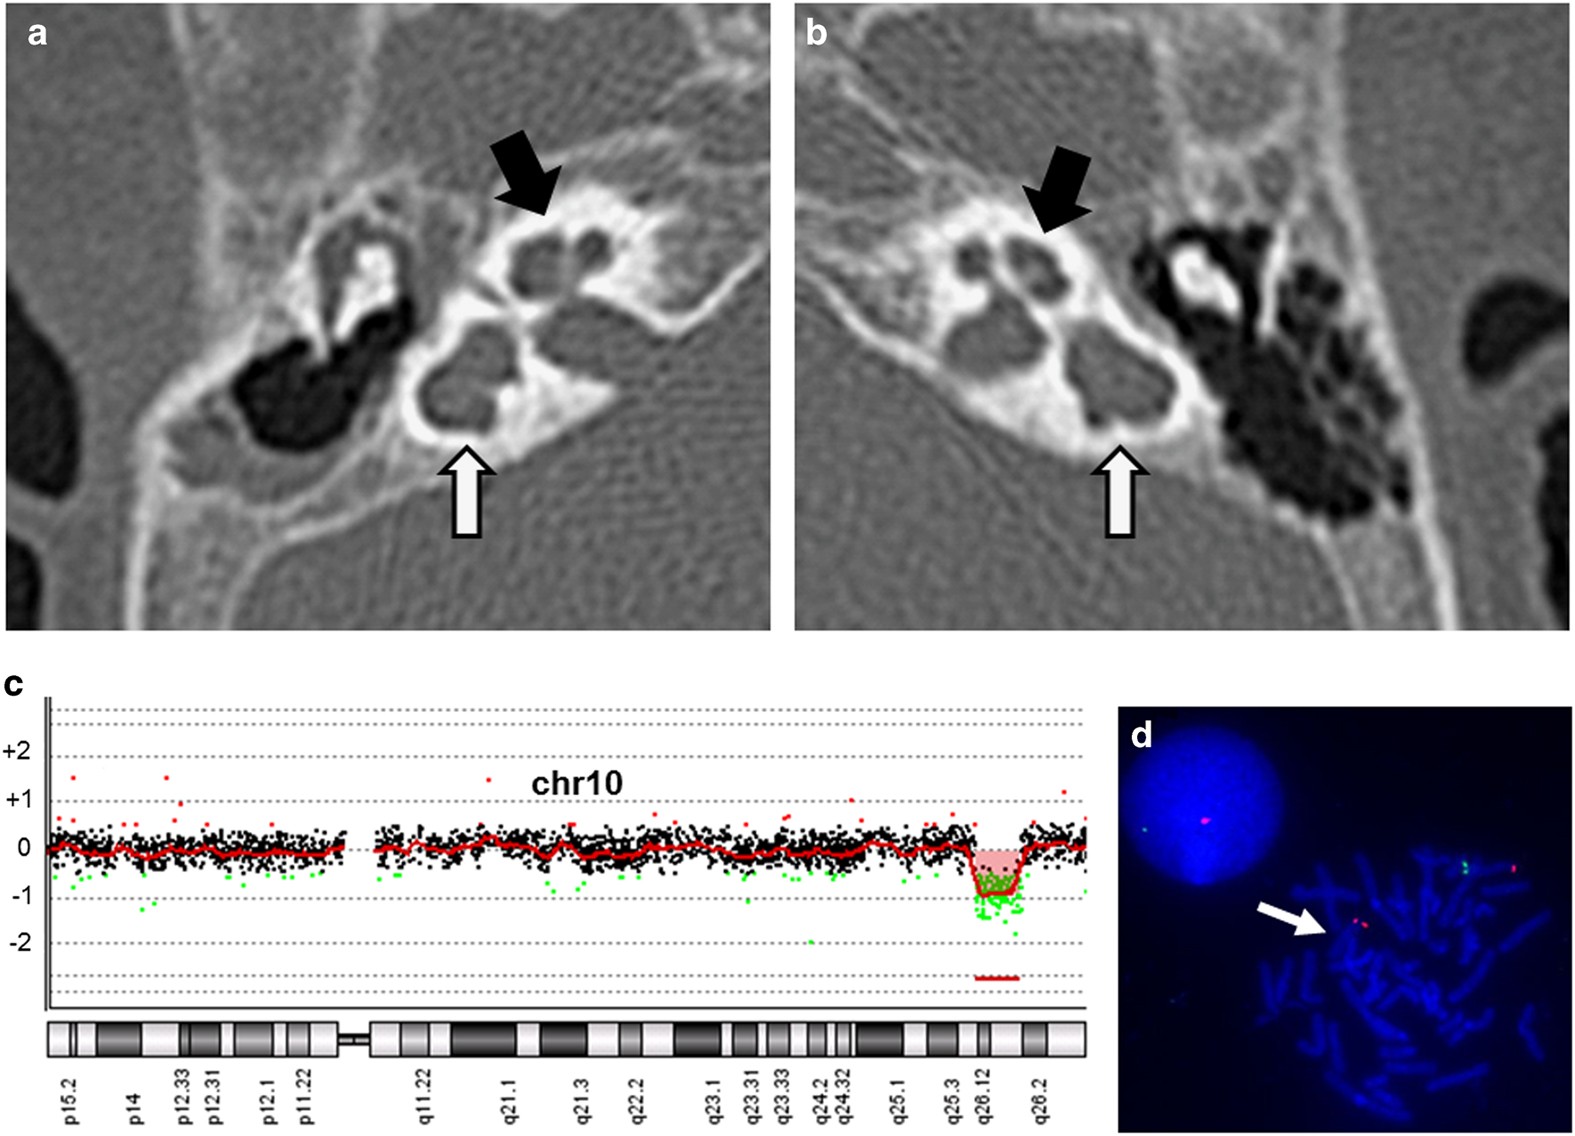

Figure 1

The results of the radiological and genetic examinations. Computed tomography scans focused on the middle ears (a; right side, b; left side) show that bilateral lateral semicircular canals are dilated, shortened and non-circular (white arrows). Bilateral anterior superior semicircular canals and bilateral posterior semicircular canals are hypoplastic (black arrows). Hypoplastic findings are extreme on the right side. (c) Loss of genomic copy number involving 10q26.11q16.13 is shown using Chromosome View by Agilent Genomic Workbench (Agilent Technologies). (d) A 10q26.11q16.13 microdeletion is confirmed by fluorescence in situ hybridization (FISH). Red signals represent markers of 10p15.3 labeled on RP11–387K19, and green signals are targets of 10q26.13 labeled on RP11–57J8. A loss of the green signal (a white arrow) indicates a deletion of this region.